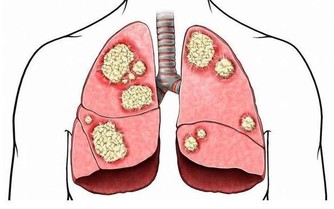

十大癌症中胃癌、大腸癌常常榜上有名,尤其大腸癌常常是罹癌之首。有關胃腸方面的癌症,大多是因為不良飲食習慣造成的。如果出現以下6種不良飲食習慣會增加患癌風險哦!

4.三餐不定時 三餐不定時不只容易讓人易胖、增加罹患糖尿病風險,更會造成胃部疾病,發生胃癌的機率大增。

6.偏愛肉食、燒烤 香腸、培根和熱狗等含有硝酸鹽及亞硝酸鹽,如果經由高溫烹調或燒烤,會產生致癌物。 飲食習慣跟健康息息相關,如果可以從生活中開始培養良好習慣,不吸菸喝酒,家中如有胃癌或腸癌病史,比起一般人更為高危險群,需要特別注意,定期追蹤檢查,才能即時治療。